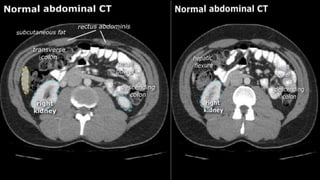

• A few characteristics of normal anatomy:

• Portal venous phase: the parenchyma of the

liver/spleen/pancreas is homogeneously enhanced.

• Intra-abdominal fat has the density of fat (HU -50 to -100;

see the X-ray/CT technique course for more information

about Hounsfield units); similar to normal subcutaneous fat.

If not, there may be ascites or fatty infiltration.

• A fewcharacteristics of normal anatomy: • Portal venous phase: the parenchyma of the liver/spleen/pancreas is homogeneously enhanced. • Intra-abdominal fat has the density of fat (HU -50 to -100; see the X-ray/CT technique course for more information about Hounsfield units); similar to normal subcutaneous fat. If not, there may be ascites or fatty infiltration.